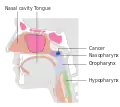

Nasopharyngeal carcinoma (NPC), or nasopharynx cancer, is the most common cancer originating in the nasopharynx, most commonly in the postero-lateral nasopharynx or pharyngeal recess (fossa of Rosenmüller), accounting for 50% of cases. NPC occurs in children and adults. NPC differs significantly from other cancers of the head and neck in its occurrence, causes, clinical behavior, and treatment. It is vastly more common in certain regions of East Asia and Africa than elsewhere, with viral, dietary and genetic factors implicated in its causation.[1] It is most common in males. It is a squamous cell carcinoma of an undifferentiated type. Squamous epithelial cells are a flat type of cell found in the skin and the membranes that line some body cavities. Undifferentiated cells are cells that do not have their mature features or functions.

Nasopharyngeal carcinoma, also known as nasopharyngeal cancer, is classified as a malignant neoplasm, or cancer, arising from the mucosal epithelium of the nasopharynx, most often within the lateral nasopharyngeal recess or fossa of Rosenmüller (a recess behind the entrance of the eustachian tube opening). The World Health Organization classifies nasopharyngeal carcinoma in three types, in order of frequency: Non-keratinizing squamous cell carcinoma; keratinizing squamous cell carcinoma; and basaloid squamous cell carcinoma.[14] The tumor must show evidence of squamous differentiation; with the non-keratinizing type (also known as lymphoepithelioma), the tumor is most strongly associated with Epstein–Barr virus infection of the cancerous cells.[15]